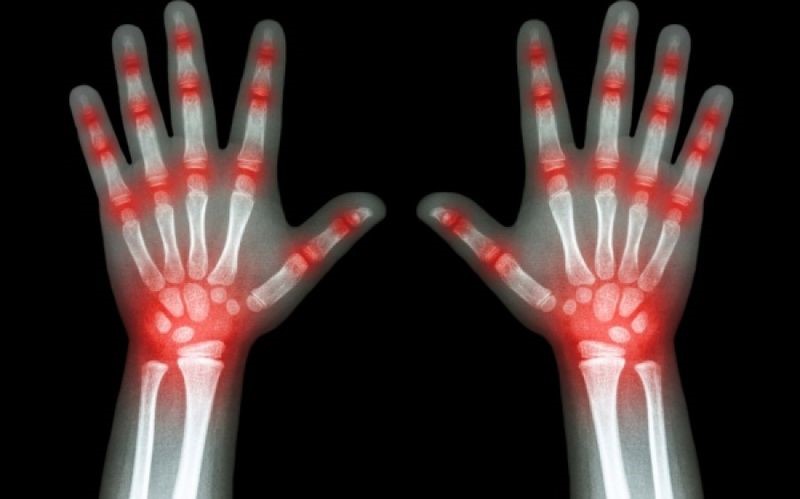

Η ρευματοειδής αρθρίτιδα αρχικά εκδηλώνεται με δυσκινησία στις μικρές αρθρώσεις (δάκτυλα) και ακολούθως στις μεγάλες (ισχία). Οι πόνοι και η δυσκινησία στις αρθρώσεις έχουν κυρίως πρωινό χαρακτήρα. Πρήξιμο, αύξηση θερμοκρασίας και παραμόρφωση των αρθρώσεων αποτελούν επίσης χαρακτηριστικά συμπτώματα της ρευματοειδούς αρθρίτιδας. Όλα τα ανωτέρω έχουν σαν αποτέλεσμα την οστεοαρθρίτιδα (καταστροφή αρθρώσεως).